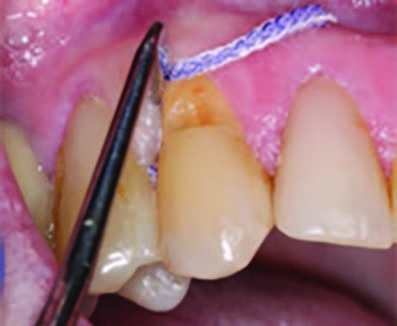

To improve isolation and soft tissue access, a retraction cord was placed before initiating the procedure (Fig. 2). The tooth was evaluated using a caries indicator dye (Kuraray Noritake Dental), helping to identify any remaining infected tissue beneath the dislodged composite (Fig. 3). Decay removal was completed with a diamond bur, and the enamel was bevelled using a starburst pattern to enhance aesthetic blending (Fig. 4). This preparation design was chosen for visual integration rather than bond strength enhancement.

Figure 2. Placement of the retraction cord to improve isolation and access to the cervical area prior to preparation.